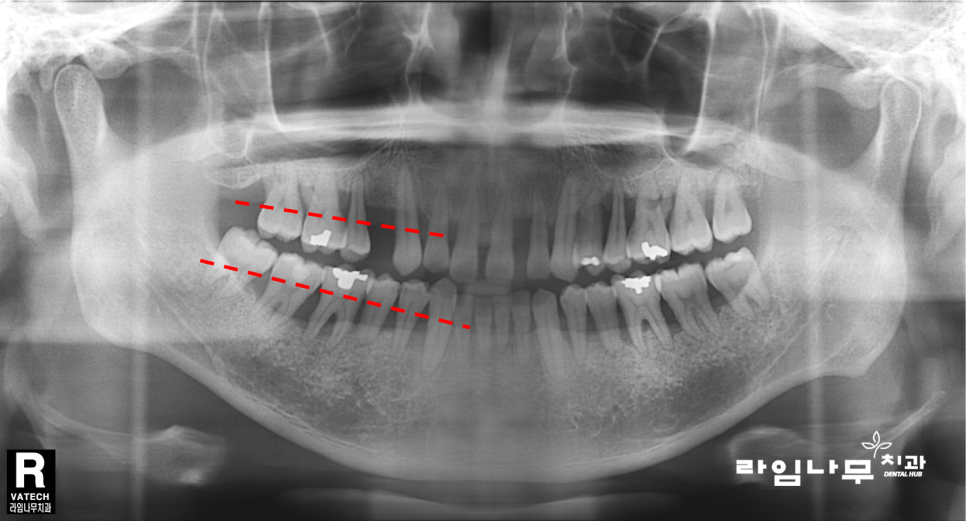

치과에서 방사선 촬영을 한 결과를 볼 때

치/아가 보이고, 치아를 붙잡아주는 잇/몸/뼈가 그 주변으로

하얗게 보여야 정상인데요,

위 엑스레이의 빨간색 점선이 정상적으로

차 있어야 할 잇/몸/뼈의 양을 나타나는데 반하여

실제 환자분의 잇.몸은 치아 뿌리를 겨우 잡고 있는 정도로

치주염으로 인해 뼈의 양이 굉장히 부족한 상태였습니다.

이제 위 사진을 다시 보시면

빨간 점선으로 표시한 사진 상 왼쪽 부분 뿐만 아니라

반대편의 경우도 뼈가 굉장히 부족한 것이 보이실거예요.

이러한 치주염의 경우 제 기능을 하지 못하는

모든 치아를 발치하고, 전체 임플란트를 하게 됩니다.